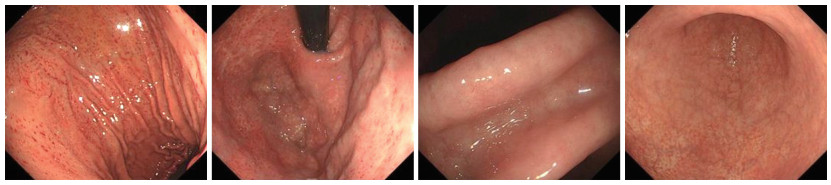

Application of BOPPPS combined with CBL teaching method in the reform of digestive system teaching in internal medicine

LIU Aiqun, GUO Xiaoyun, TANG Xiping, SHEN Yanhua, WEI Lining, ZHONG Yi, HUANG Yueli, XIE Weishun, ZHONG Dani

2025, 23(10): 1773-1776. doi: 10.16766/j.cnki.issn.1674-4152.004226

76 1

Abstract:

Objective  The BOPPPS model, characterized by its student-centered approach and emphasis on full student participation, is increasingly applied in classroom teaching. When combined with CBL (Case-Based Learning), teachers can adjust the teaching implementation according to classroom real-time feedback to achieve better teaching effects. Based on this situation, this study aimed to explore the practical application and effectiveness of the BOPPPS combined with CBL blended teaching mode in the teaching of digestive system-upper gastrointestinal bleeding, with the goal of informing future reforms in clinical teaching.  Methods  A total of 229 students majoring in clinical medicine from the School of Oncology, Guangxi Medical University in 2020, were selected as the research objects, and classes were randomly grouped using computer software to generate random numbers. They were randomly divided into the experimental group A (BOPPPS combined with CBL, 113 students) and the control group B (traditional mode teaching, 116 students). At the end of the teaching period, a combination of questionnaires and a theoretical knowledge examination was used to evaluate teaching effectiveness.  Results  The satisfaction survey showed that students in the experimental group were more satisfied with the overall course experience, course content, and teaching method than those in the control group (all P < 0.05). In the post-class examination, the scores in the experimental group was significantly higher than that of the control group, with significant differences(81.53±5.16 vs. 79.28±9.96, t=2.137, all P < 0.05).  Conclusion  In the context of digestive system teaching, the BOPPPS combined with CBL blended teaching demonstrates greater effectiveness than the traditional method. It promotes students ' engagement and participation, and is well-suited for promotion and application in the clinical teaching of internal medicine.